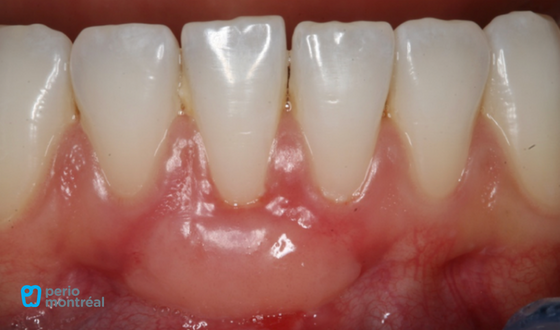

This patient “L.P.” presented with a chief complaint of “I bit in to a peach and caused this recession”. There is a Miller Class II recession defect on tooth #41 with a lack of keratinized tissue. The patient reports mild sensitivity to brushing.

- Miller Class II recession tooth #41

- Lack of keratinized tissue #41